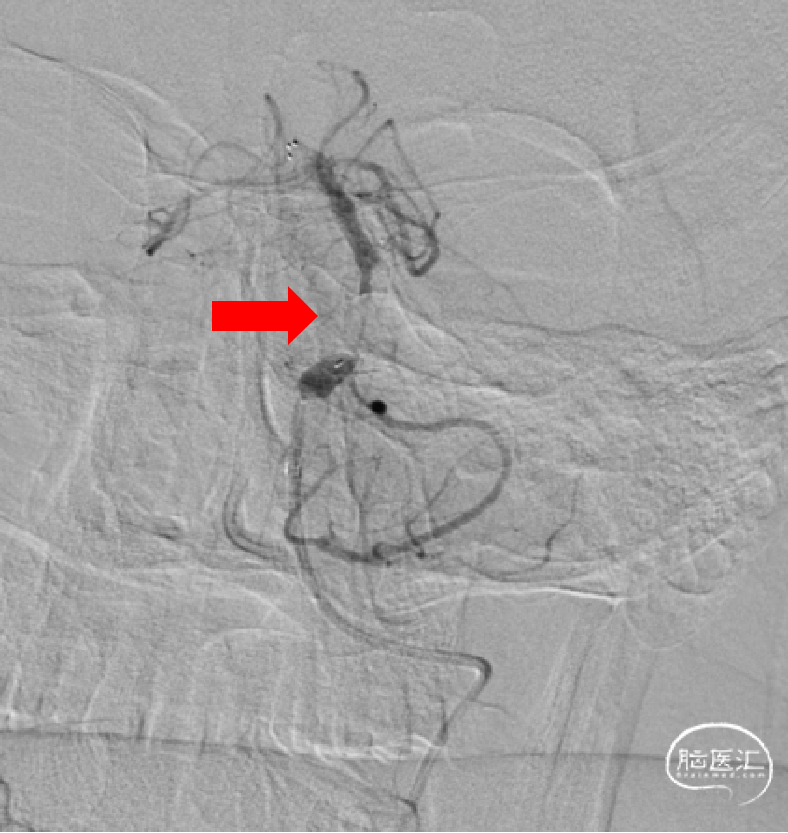

1、选择右侧椎动脉入路;2、造影提示V4段近端狭窄,远端未见显影。

1、ACE60抽吸导管插至右侧椎动脉V4段,微导丝导丝反复尝试未能越过闭塞段;2、考虑右侧椎动脉V4段远端完全闭塞。

右侧颈动脉造影未见明显后交通开放,可见基底动脉末端显影(红色箭头)。